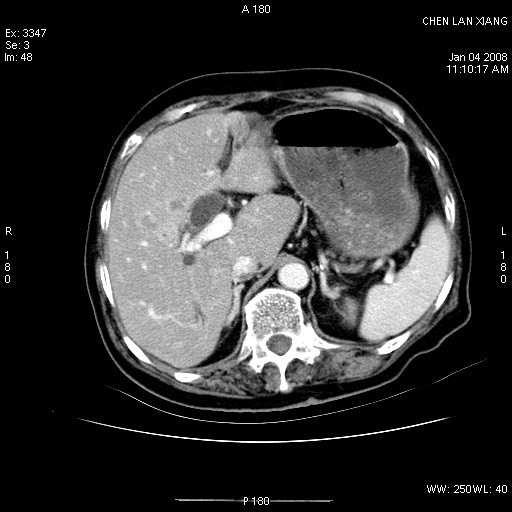

女,76岁,腹痛3-4天,b超示:肝内实性肿物,胆囊强回声,胆总管扩张.

考虑:1、胆总管下端结石伴梗阻性肝内外胆管扩张(肝左叶外侧段肝内胆管多发结石、胆管炎);

2、肿囊癌累及肝,不除外 黄色肉芽肿性胆囊炎。

1 胆总管末端结石伴肝内胆管结石,肝内外胆管扩张。2 胆囊扩大,胆囊壁不规则增厚,内见软组织密度影。考虑:慢性胆囊炎,不除外胆囊癌!

标题: 肝右叶病灶

胆囊癌侵犯肝右叶?

1)胆囊癌伴肝脏转移。2)胆总管下端结石、肝内胆管结石伴肝内外胆管扩张。